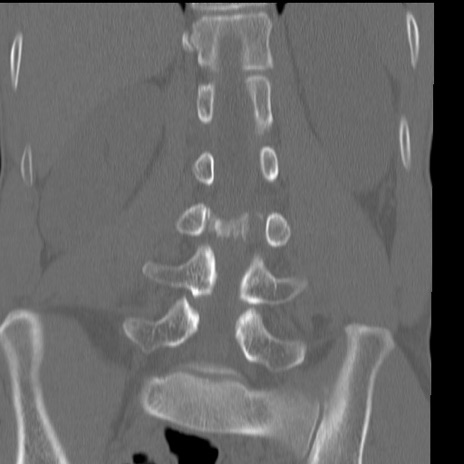

症例3 腰椎CT(冠状断像)

腰椎CT